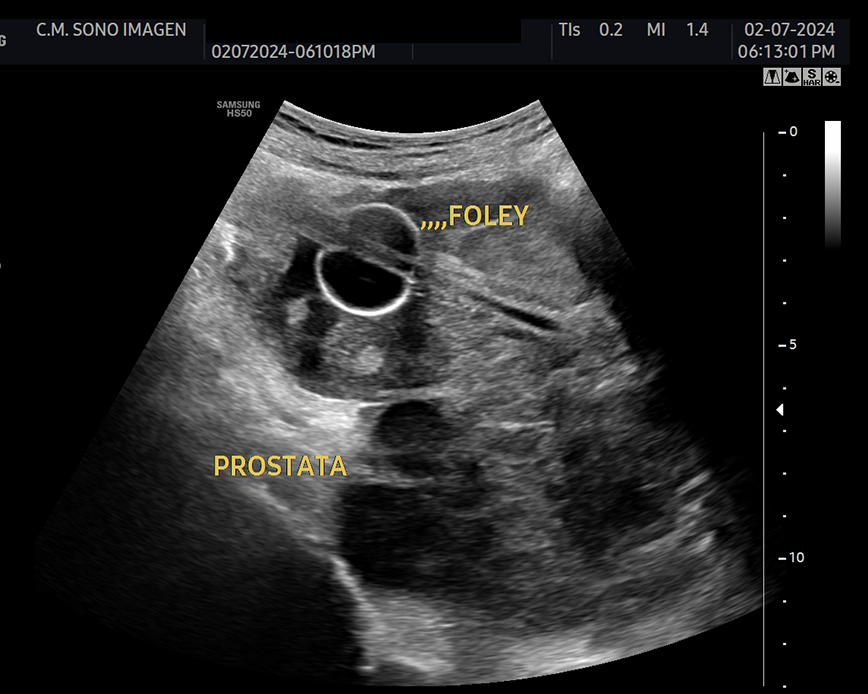

Ecografía Prostática

- hiperplasia prostática benigna(HPB)

- dificultad para orinar o retención urinaria

- control postquirúrgico o postratamiento